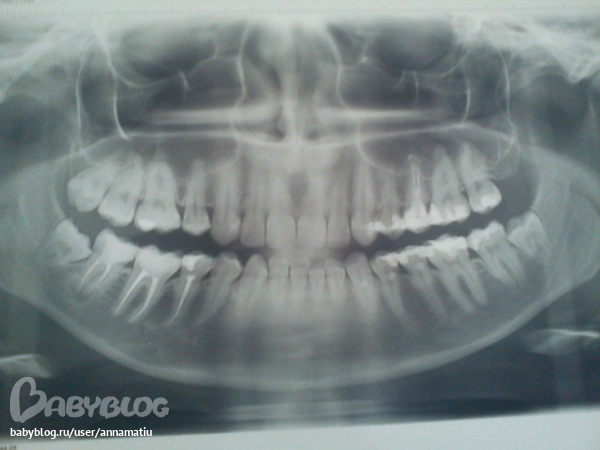

Здравствуйте, Алина Владимировна. Помогите, пожалуйста разобраться. Я недавно залечила 5, 6 и 7 зубы слева внизу. И спустя неделю, мне стало больно накусывать предположительно 6 зуб, но не всегда( иногда ем нормально, а иногда больновато). И реагирует на холод. До лечения ни один зуб не беспокоил. Скажите, какой зуб может давать болезненность и нужно ли удалять в нём нерв . Очень жду вашего совета, так как планирую беременность.

На снимке меня вот, что смутило

В 6 зубе пломба стоит пряяяяяям на роге пульпы, это может давать боль.

В 7 зубе смущает неоднородность пломбировочного материала.

На 7 снизу справа зубе киста!!!! Сделайте прицельный рентгеновский снимок, если там такая же картина- перелечивать зуб обязательно.

Горизонтальные стрелки указывают на возможный кариес на контактных поверхностях зуба.